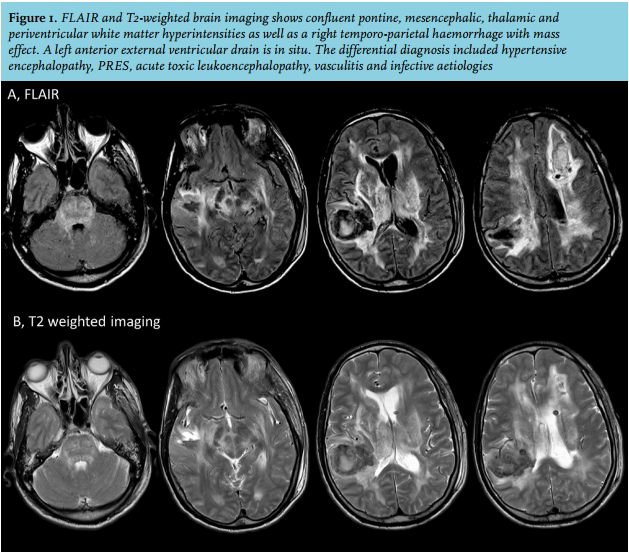

His urgent MRI brain scan revealed confluent pontine, mesencephalic, thalamic and periventricular white matter hyperintensities on FLAIR and T2-weighted brain imaging in addition to the right temporo-parietal haemorrhage (figure 1). Based on the MRI findings, the differential diagnosis included hypertensive encephalopathy, posterior reversible encephalopathy syndrome (PRES), acute toxic leukoencephalopathy, vasculitis and infective aetiologies, including fungal and flavivirus infections.